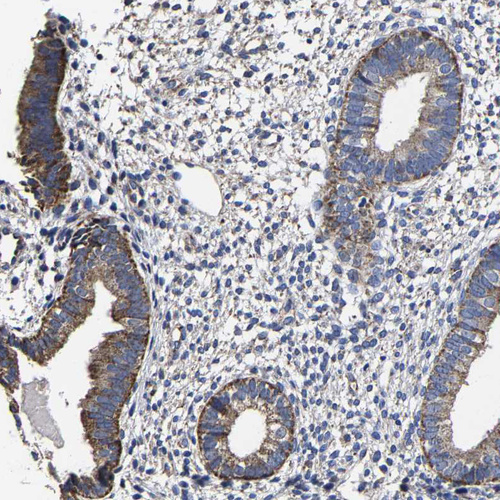

Immunohistochemistry analysis in human liver and skeletal muscle tissues using HPA020728 antibody. Corresponding AASS RNA-seq data are presented for the same tissues.